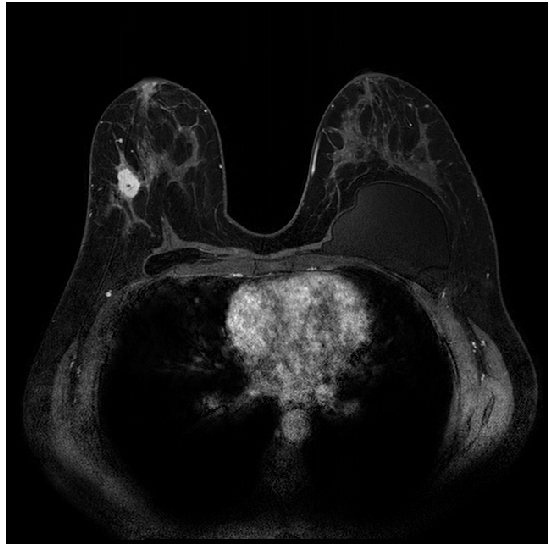

Assessment of the MTL method was performed on 1.5T and 3T DCE-MRI datasets of 447 and 193 breast lesions, respectively (Table 1). The DCE-MR images were acquired at the University of Chicago Medical Center over a span of 6 years from 2006 to 2012 on either 1.5T or 3T Philips scanners with T1-weighted spoiled gradient sequence. Each lesion was characterized as benign or malignant based on pathology from biopsy. Examples of 1.5T and 3T images of cancerous lesions are shown in Figure 1.